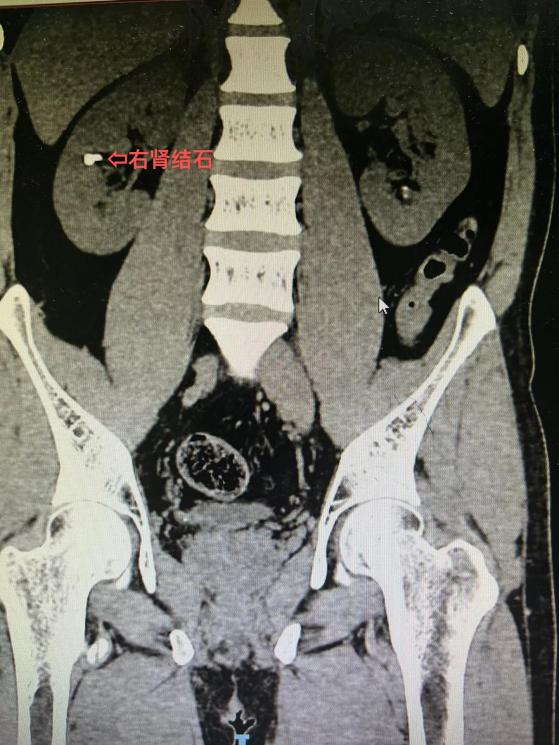

10 年前患者检查发现双肾结石,近年来反复出现腰部疼痛,在外院多次行体外冲击波碎石,未见结石排出,症状也没有改善,严重影响了工作和生活。后到 市中医医院 泌尿外科就诊,泌尿外科拓鹏飞副主任医师接诊后行 CT 显示:双肾多发结石、右侧输尿管结石。